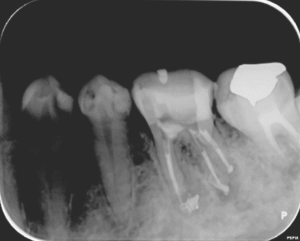

根の治療1か月後にグラスファイバーの芯棒を用いた歯の土台(根の治療を行った場合に行う治療です)を立てた際のレントゲン写真です。まだ根の先の骨の溶けている部分の大きさは変わりません。

根の治療2か月後のレントゲン写真です。矢印の部分の骨の溶けている部分の大きさが小さくなっています。

根の治療4か月後のレントゲン写真です。骨の溶けている部分の透過性(黒さ)が改善して(薄くなって)、治癒に向かっている様子がうかがえます。治療後から咬む際の痛みなどの症状は無くなり、治療後2カ月で仮歯を装着されています。